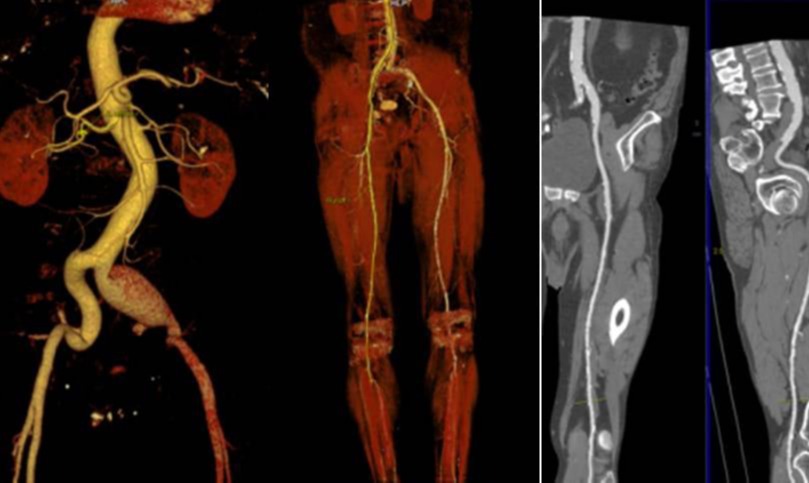

Αγγειοπλαστική λαγονίων, μηριαίων και κνημιαίων αρτηριών

Η αγγειοπλαστική των λαγονίων, μηριαίων και κνημιαίων αρτηριών αναφέρεται στη χειρουργική επέμβαση που προορίζεται για την αντιμετώπιση αρτηριακών προβλημάτων σε αυτές τις περιοχές. Η διαδικασία συνήθως περιλαμβάνει τη χρήση αγγειοπλαστικών τεχνικών για τη διόρθωση στενώσεων ή αποκλεισμών στις αρτηρίες, με στόχο τη βελτίωση της κυκλοφορίας του αίματος.

Οι αρτηριακές στενώσεις (στένωση των αγγείων) μπορεί να προκαλούνται από την αθηροσκλήρωση, η οποία συχνά σχετίζεται με την απόθεση αθηροματικών πλακών στο εσωτερικό των αρτηριών. Η αγγειοπλαστική είναι μια τεχνική που χρησιμοποιείται για την επαναφορά της φυσιολογικής ροής του αίματος στις περιοχές που επηρεάζονται από αυτές τις στενώσεις.

Η διαδικασία της αγγειοπλαστικής συχνά περιλαμβάνει τη χρήση ενός καθετήρα, ο οποίος εισάγεται στην αρτηρία μέσω μιας μικρής τομής. Στη συνέχεια, ο γιατρός χρησιμοποιεί ειδικά εργαλεία για να επεκτείνει τη στενωτική περιοχή ή να αφαιρέσει το αθηροματικό υλικό. Σε ορισμένες περιπτώσεις, επίσης, μπορεί να χρησιμοποιηθούν στεντ για τη διατήρηση της ανοιχτής αρτηρίας.

Η αγγειοπλαστική μπορεί να βοηθήσει στην αντιμετώπιση προβλημάτων κυκλοφορίας του αίματος, ελαττώνοντας τον κίνδυνο επιπλοκών όπως οι καρδιακές προσβολές ή οι εγκεφαλικοί προσβολές. Είναι σημαντικό να σημειωθεί ότι η απόφαση για τη διεξαγωγή αγγειοπλαστικής λαμβάνεται με βάση την κλινική εικόνα του ασθενούς και τις ευκαιρίες για την εφαρμογή αυτής της μεθόδου.